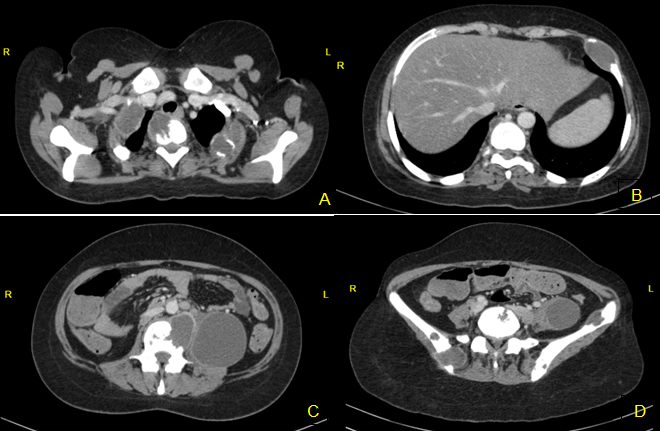

Computed tomography (CT) scan of the chest, abdomen and iliac bone confirmed multiple expansive, destructive hypodense mass or abscess lesion on the right 1st, 2nd, 4th ribs, the left 1st, 2nd, 6th ribs and 1st, 2nd, 6th, 10th, 12th thoracic vertebrae, 1st, 2nd, 3th, 4th lumbar vertebrae, the left and the right iliac bones (Figure 1A–D). Additionally, there was a 8x7 cm hypodense area compatible with abscess or hematoma on the left psoas muscle and along the left iliopsoas muscle.

Figure 1: (A) Contrast-enhanced computed tomography axial images. Destructive hypodense mass or abscess lesion on the right 1st, 2nd ribs and 2nd thoracic vertebra corpus, (B) At the left 6th rib (FNAB applied), (C) L3 lumbar vertebra corpus and abscess on the left psoas muscle, (D) On the left and the right iliac bones and abscess in the left iliopsoas muscle.